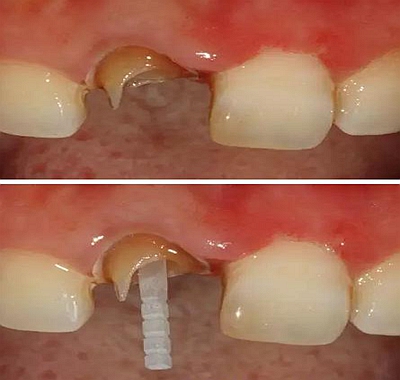

在操作的過(guò)程中要注意無(wú)菌操作,保證纖維樁的無(wú)菌狀態(tài)。推薦將樹(shù)脂核堆好之后再截?cái)嗬w維樁,而不是截?cái)嗪笤僬辰?。如下圖: